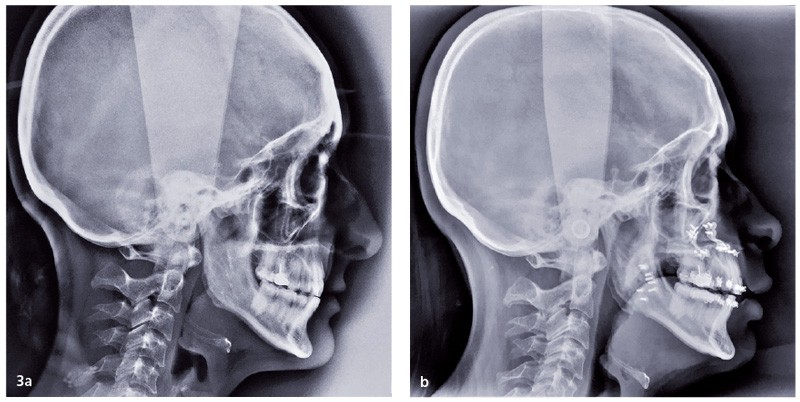

• Une amélioration immédiate des troubles du sommeil et de la qualité de vie des patients porteurs d’un Syndrome d’Apnées Hypopnées Obstructives du Sommeil (SAHOS) liée à l’augmentation des dimensions des voies aérifères supérieures par l’avancée mandibulaire et/ou maxillaire (fig. 3).